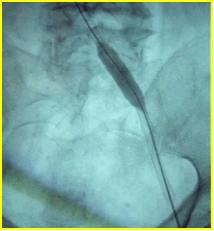

急诊造影:大腿段腘静脉通畅,股静脉通畅,见图3

图3